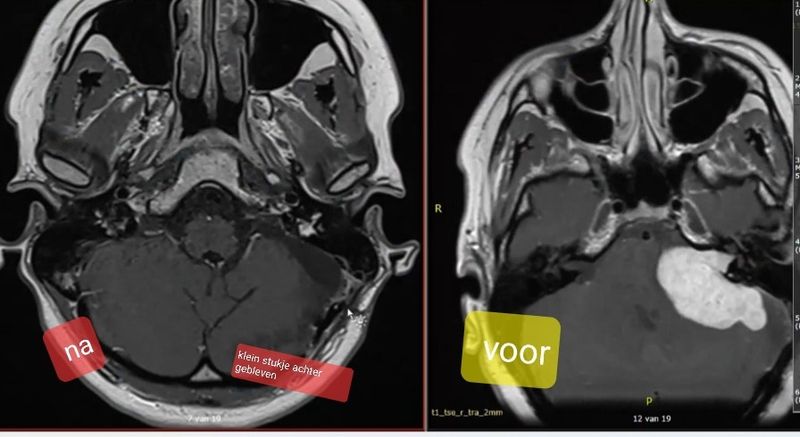

Het ging een tijdje erg goed. Ik had goed nieuws ontvangen: de tumor was gelijk gebleven. Op dat moment besloot ik om de opleiding verpleegkundige op te pakken en eindelijk mijn droombaan een stukje dichterbij te halen. Een lange route maar ik wist: ik kom er wel! Ik moet zeggen, ik heb altijd een hele positieve instelling gehad. Na een jaar bezig te zijn met de opleiding werd de grond helaas volledig onder mijn voeten uit getrapt. Mijn tumor was fiks gegroeid en er zat niets anders op dan wéér onder het mes te gaan. Mijn vorige operatie, in 2012, veroorzaakte dat ik mijn studie (verpleegkunde) niet kon vervolgen. En dit was waarschijnlijk nu weer mijn uitzicht.